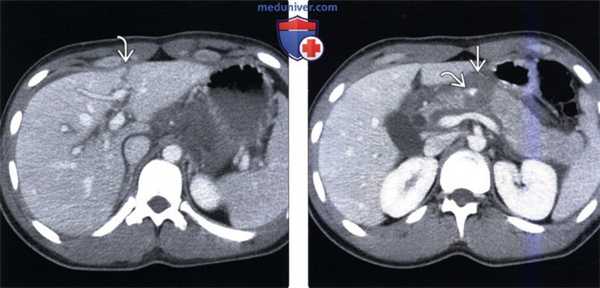

(Слева) На аксиальной КТ с контрастным усилением определяется разрыв, проходящий через левую долю печений.

(Справа) На аксиальной КТ с контрастным усилением у этого же пациента определяется разрыв шейки поджелудочной железы, проходящий вплоть до селезеночной вены. Поджелудочная железа полностью фрагментирована, определяются признаки активной экстравазации. Разрыв левой доли печени часто сочетается с повреждениями других органов, расположенных по средней линии.